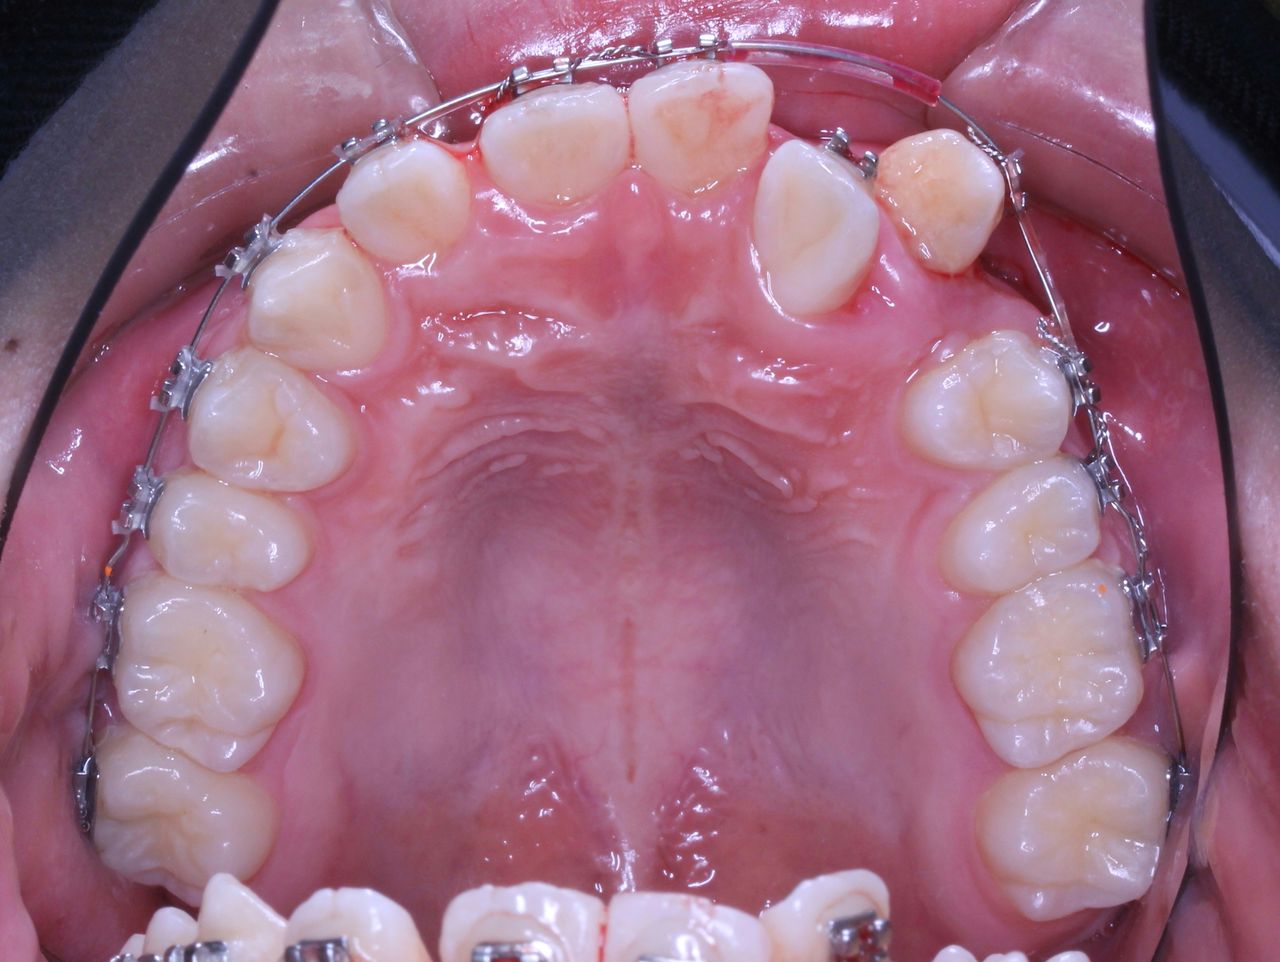

現在の状況はもう少し治療が進んでいるのですが、矯正歯科ネットユーザー様からの質問が昨日でしたので、数か月前の記録ですが、現在の進行状況です

正面と側面の写真をみてもあまり変化がわからないと思います。

上からみてみるとどうでしょうか?

もう少し犬歯が後方に移動してもらえると、2番目の歯が前方に移動可能な感じです